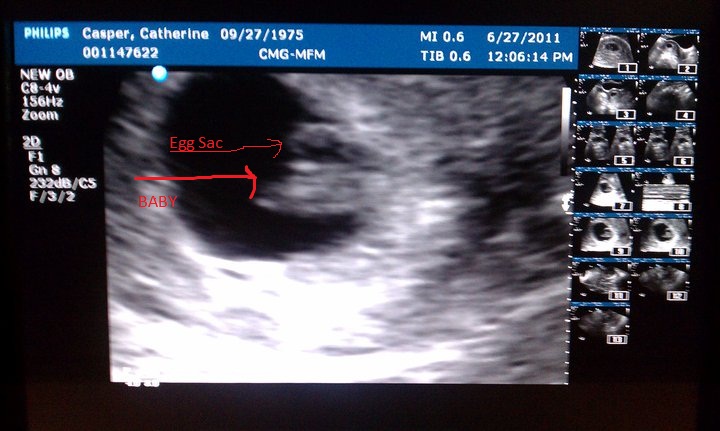

Wes and I are expecting our second baby. All my blood work up came back today as excellent. And I had an ultrasound this past Monday. Baby is progressing, perfectly. I was able to see the heart beating on the monitor and it was amazing! 152 beats a minute. Very strong and healthy! I just wish the stomach sickies would end and my vertigo would go away. Other then that, it's been okay. LOL

Due on Feb. 14th, 2012. Yes, Valentine's Day!

Attached Images

File Type: jpg Baby Casper 6-27-2011.jpg (93.2 KB, 400 views)